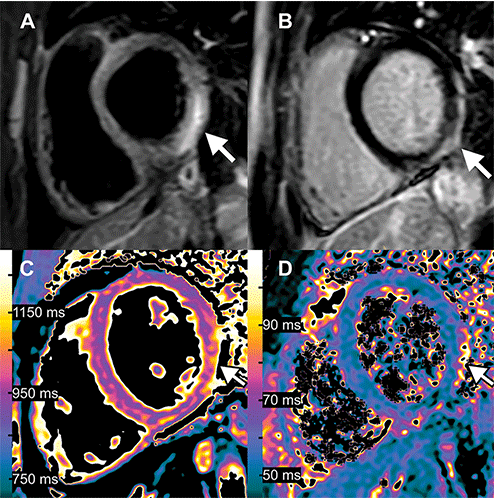

Images in 15-year-old boy with myocarditis after COVID-19 vaccination. One day after receiving his second vaccination dose, he developed fever, myalgia, and intermittent tachycardia. (A) T2-weighted short inversion time inversion recovery MRI scan at 1.5 T in short-axis view shows focal high-signal intensities (arrow) at basal lateral and inferior wall, indicating myocardial edema. (B) Late gadolinium enhancement image in short-axis view shows corresponding linear subepicardial enhancement (arrow), indicating inflammatory myocardial necrosis. (C) T1 mapping and (D) T2 mapping in short-axis view show elevated T1 and T2 at the mid ventricular lateral and inferolateral wall (arrow in C and D), indicating acute myocardial injury (focal T1, 1165 msec; focal T2, 70 msec; institution-specific cutoff values for acute myocarditis: T1global ≥1000 msec, T2 global ≥55.9 msec). https://doi.org/10.1148/radiol.229031 ©RSNA 2022

The first runner-up is an article entitled, “Myocarditis Following COVID-19 Vaccination,” by Alexander Isaak, Andreas Feisst and Julian A. Luetkens. 2022 marks the third consecutive year in which a COVID-related image was honored among top contenders for Images in Radiology, and this article attracted the most social media attention among all 2022 Images in Radiology receiving an Altmetric score placing it in the top 1% of all research outputs of the same age.